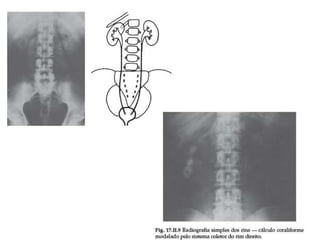

Exames de imagem

•   Rx simples.

•   Ultra-sonografia.

•   Cintilografia renal.

•   Tomografia computadorizada.

•   Urografia excretora.

•   Uretrocistografia miccional.

Exames de imagem • Rx simples. • Ultra-sonografia. • Cintilografia renal. • Tomografia computadorizada. • Urografia excretora. • Uretrocistografia miccional.